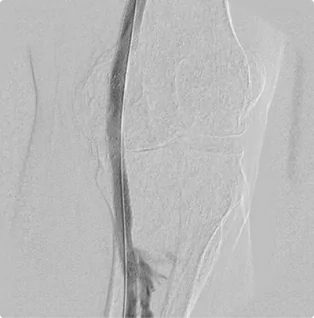

Male – Age 86

Referred by his Podiatrist for his Varicose Veins and Pre-Podiatric Surgical Evaluation

Although this patient was first referred for suspected venous disease, his first ultrasound revealed critical arterial disease in the left calf that placed him at high risk for amputation. The tibial arteries- the branches of arteries that deliver blood to the front and back of the calf- were completely shut off, starving the lower leg of blood and causing severe pain. He was scheduled for intervention the next week. After treating the arteries down the leg and into the foot with atherectomy, angioplasty, and stent placement, Dr. Goldstein restored flow through all three arterial branches and down into the foot. Proper circulation was restored, and the foot was salvaged. Since the first treatment, Dr. Goldstein has closely monitored flow through the arteries to maintain a healthy flow.

Before

Arterial flow through the calf after the intervention. All three arterial branches are present and flowing smoothly, delivering proper flow to the calf and down into the foot to eliminate the need for amputation.

After

Arterial flow through the foot after the intervention. All three arterial branches are present and flowing smoothly, delivering proper flow to the calf and down into the foot to eliminate the need for amputation.